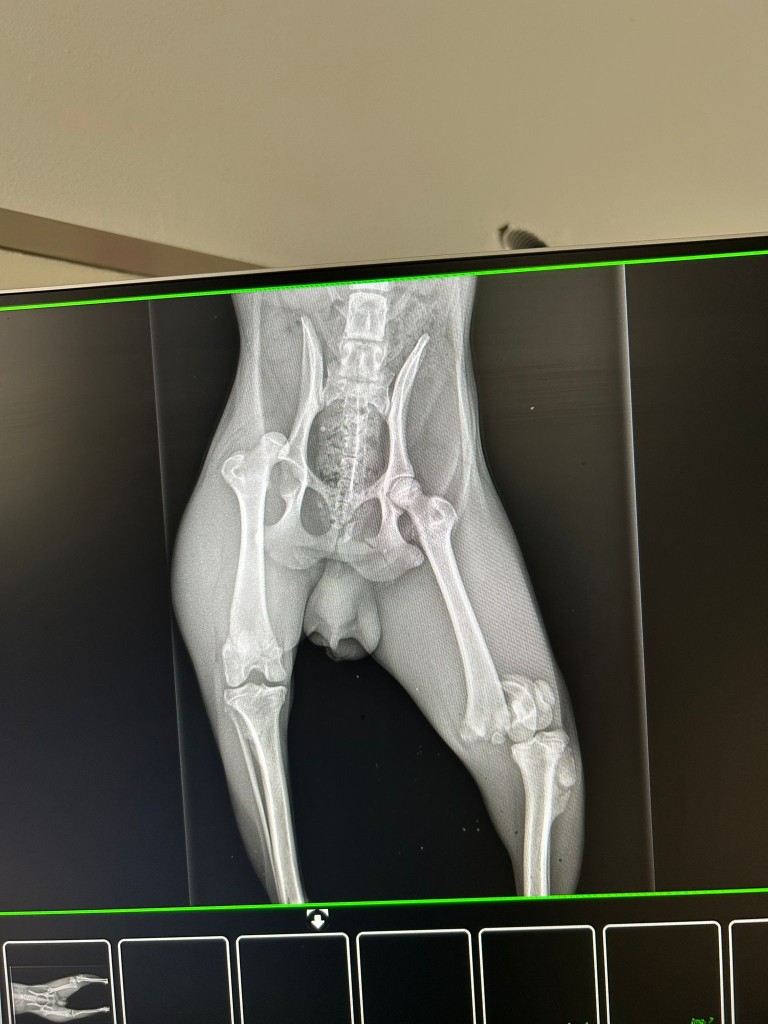

Il souffre d’une fracture du fémur et d’une luxation sur l’autre patte .